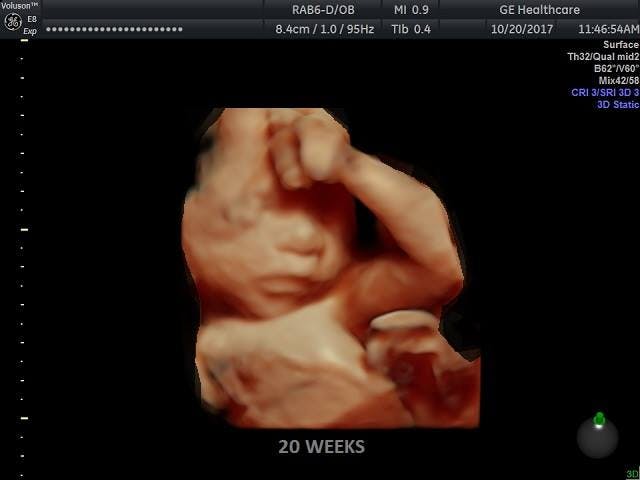

3) Planned Parenthood actually does abort babies who could survive outside the womb.

Famous Nilsson photo of a preborn baby at 20 weeks

Live Action News investigated Planned Parenthood’s own clinic websites, finding that at least six PP clinics throughout the nation do in fact provide abortions after viability. These clinics (screenshots here), perform abortions at 22 weeks, 6 days; 23 weeks, 6 days; and 24 weeks.

Viability is the point in time where babies could survive outside the womb. According to a fact-check article on Richards’ statement:

[F]etal respiratory capacity has been enhanced in our modern day. A great number of babies can now survive at 22 weeks gestation. (The earliest recorded babies to survive were born at 21 weeks 6 days and 21 weeks 5 days.) The Washington Post remarkably even reported: “That babies can survive at 22 weeks is not a new finding; it has been known for 15 years. … New research confirmed that 22-week fetuses, measured from the first day of the pregnant woman’s last menstrual cycle, can survive.”